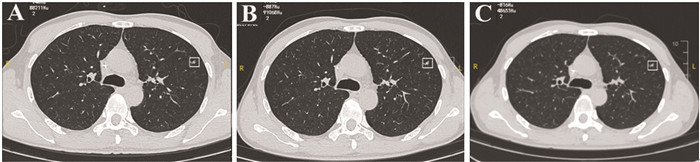

高级别肉瘤患者肺部不确定性质结节胸部CT影像学特征与转归:一项单中心回顾性研究

目的 分析肺部高级别软组织肉瘤患者肺部不确定性质结节(IPN)的影像学特征与转归。

方法 回顾性分析82例伴IPN的高级别肉瘤患者的临床资料,IPN的CT影像学特征以及转归。

结果 IPN平均大小6.453±0.864 mm。IPN直径、形状、密度及结节发现间期可能是恶性转归相关的CT影像特征。年龄(HR=1.047, 95%CI: 1.007~1.088)与结节发现间期(HR=3.194, 95%CI: 1.052~9.694)是影响恶性IPN患者生存期的独立因素。

结论 胸部CT的影像学特征可能为良恶性结节性质和生存预后的判断提供重要指导意义。